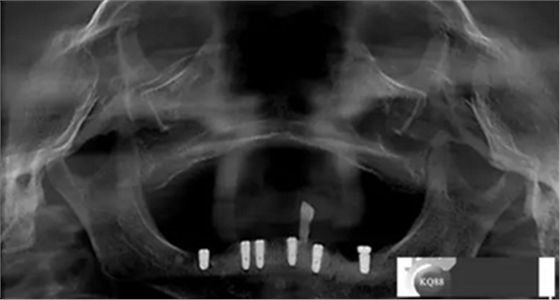

3,治療計劃:依據(jù)檢查及主訴,擬323436434446植入6顆osstem植體,無即刻拔除33殘冠目的方便戴過渡性臨時活動義齒,6個月后完成二氧化鋯冠橋修復

2)術前準備及手術過程,測量血壓及血糖,簽種植知情同意書;嚴格遵循無菌操作,局麻下采用微創(chuàng)技術于323436分別植入osstem4.0X10,4.0X10,4.5X7; 434446分別植入osstem4.0X1O,4.0X10,4.5X7.初期穩(wěn)定性均達到了35N.CM以上;嚴密縫合,止血,種植體位點和方向與設計一致。

4)三個月后行種植二期手術并拔除33殘冠,于34364346種植體接入成品基臺,調改活動義齒做一個改良式的套筒冠覆蓋義齒。